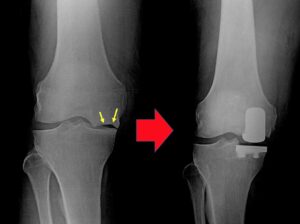

Total Knee Replacement (TKR), also known as knee arthroplasty, is a surgical procedure that replaces the entire knee joint with an artificial prosthesis to relieve pain and improve function. This procedure is typically recommended for individuals suffering from severe knee pain and limited mobility due to conditions such as osteoarthritis, rheumatoid arthritis or traumatic injury.

Preoperative Preparation : Patients undergo a thorough evaluation, including imaging tests like X-ray or MRI or Citi scan, blood work and consultations to ensure they are suitable candidates for surgery. Physical preparation, such as strengthening exercises, may also be recommended.

Resurfacing : Damaged bone and cartilage are removed from the femur, tibia and patella. Metal components are then attached to the ends of these bones and a plastic spacer is placed in between them to create a smooth surface for movement.